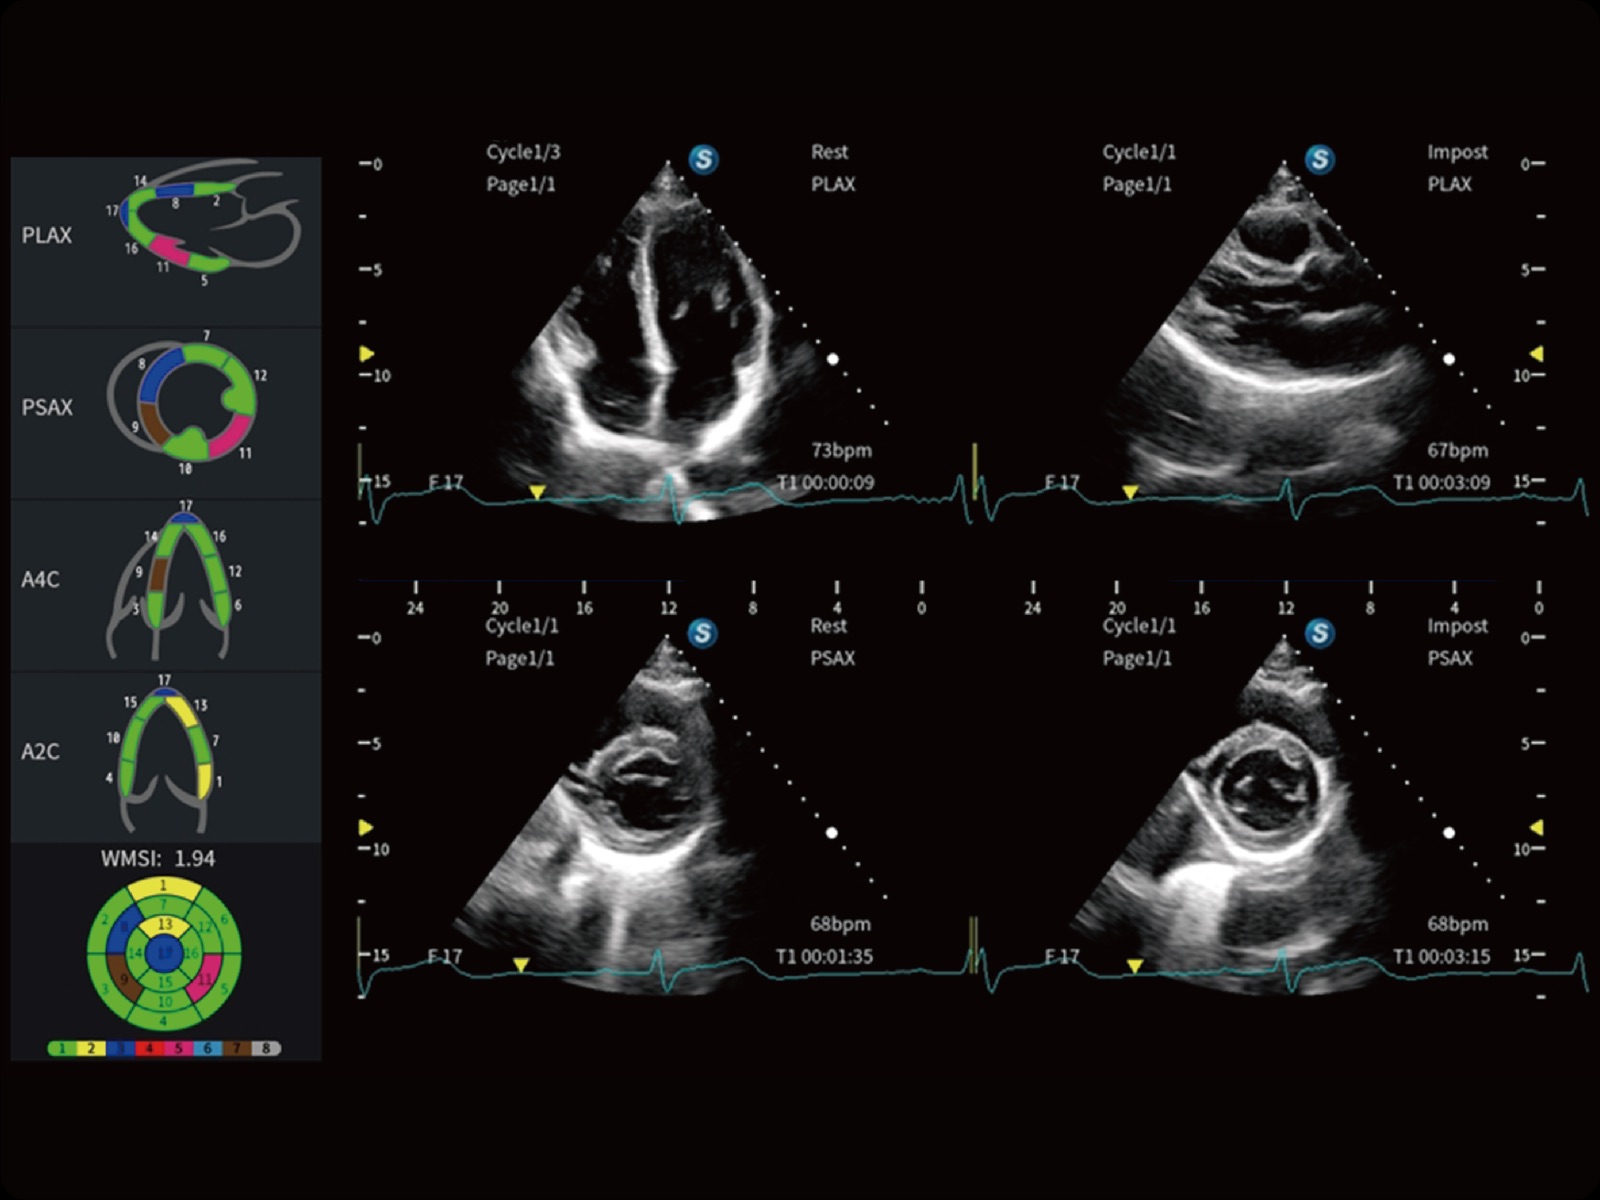

心脏应用